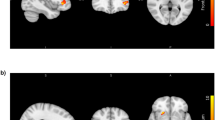

The neural endophenotype is made up of grey matter regions and regions of activation derived from the MID task. Grey matter regions contributing to this neural endophenotype were located bilaterally in the cerebellum, amygdala, hippocampus, para-hippocampus and orbital frontal cortex, which all present bilaterally. There was also a largely left lateralised grey matter cluster in the inferotemporal cortex. sPLS weights in each of these brain regions were negative, implying an inverse association between PRS scores/phenotypes and grey matter. Neural endophenotype clusters that came up in the MID task were largely left lateralised and included the fusiform gyrus and para-hippocampus, postcentral and parietal inferior, calcarine and occipital superior and frontal superior medial cortex. These results are displayed in Fig. 2. sPLS weights in each of these brain regions were positive, implying a positive association between the MID contrast map and the PRS/phenotype scores. The full set of VBM and MID clusters identified and localised in the sPLS analysis are tabulated in Supplementary Tables S1 and S2.

a The scatter plots in panel (a) of the figure show relations between neuroimaging and ADHD and BMI PRS scores. b The brain regions in panel (b) of the figure illustrate the VBM and MID regions that are associated with ADHD and BMI PRS scores, and their associated phenotypes. c The scatter plots in panel (c) of the figure show relations between neuroimaging and ADHD and BMI phenotypes